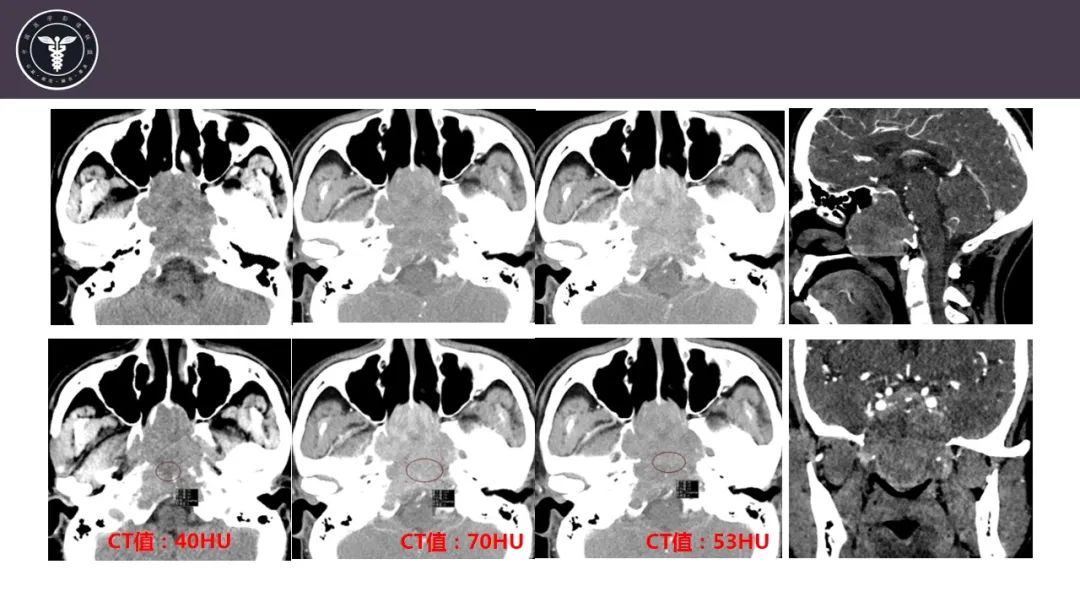

【病例】斜坡区骨巨细胞瘤 VS 脊索瘤-3

【病例】斜坡区骨巨细胞瘤 VS 脊索瘤-4